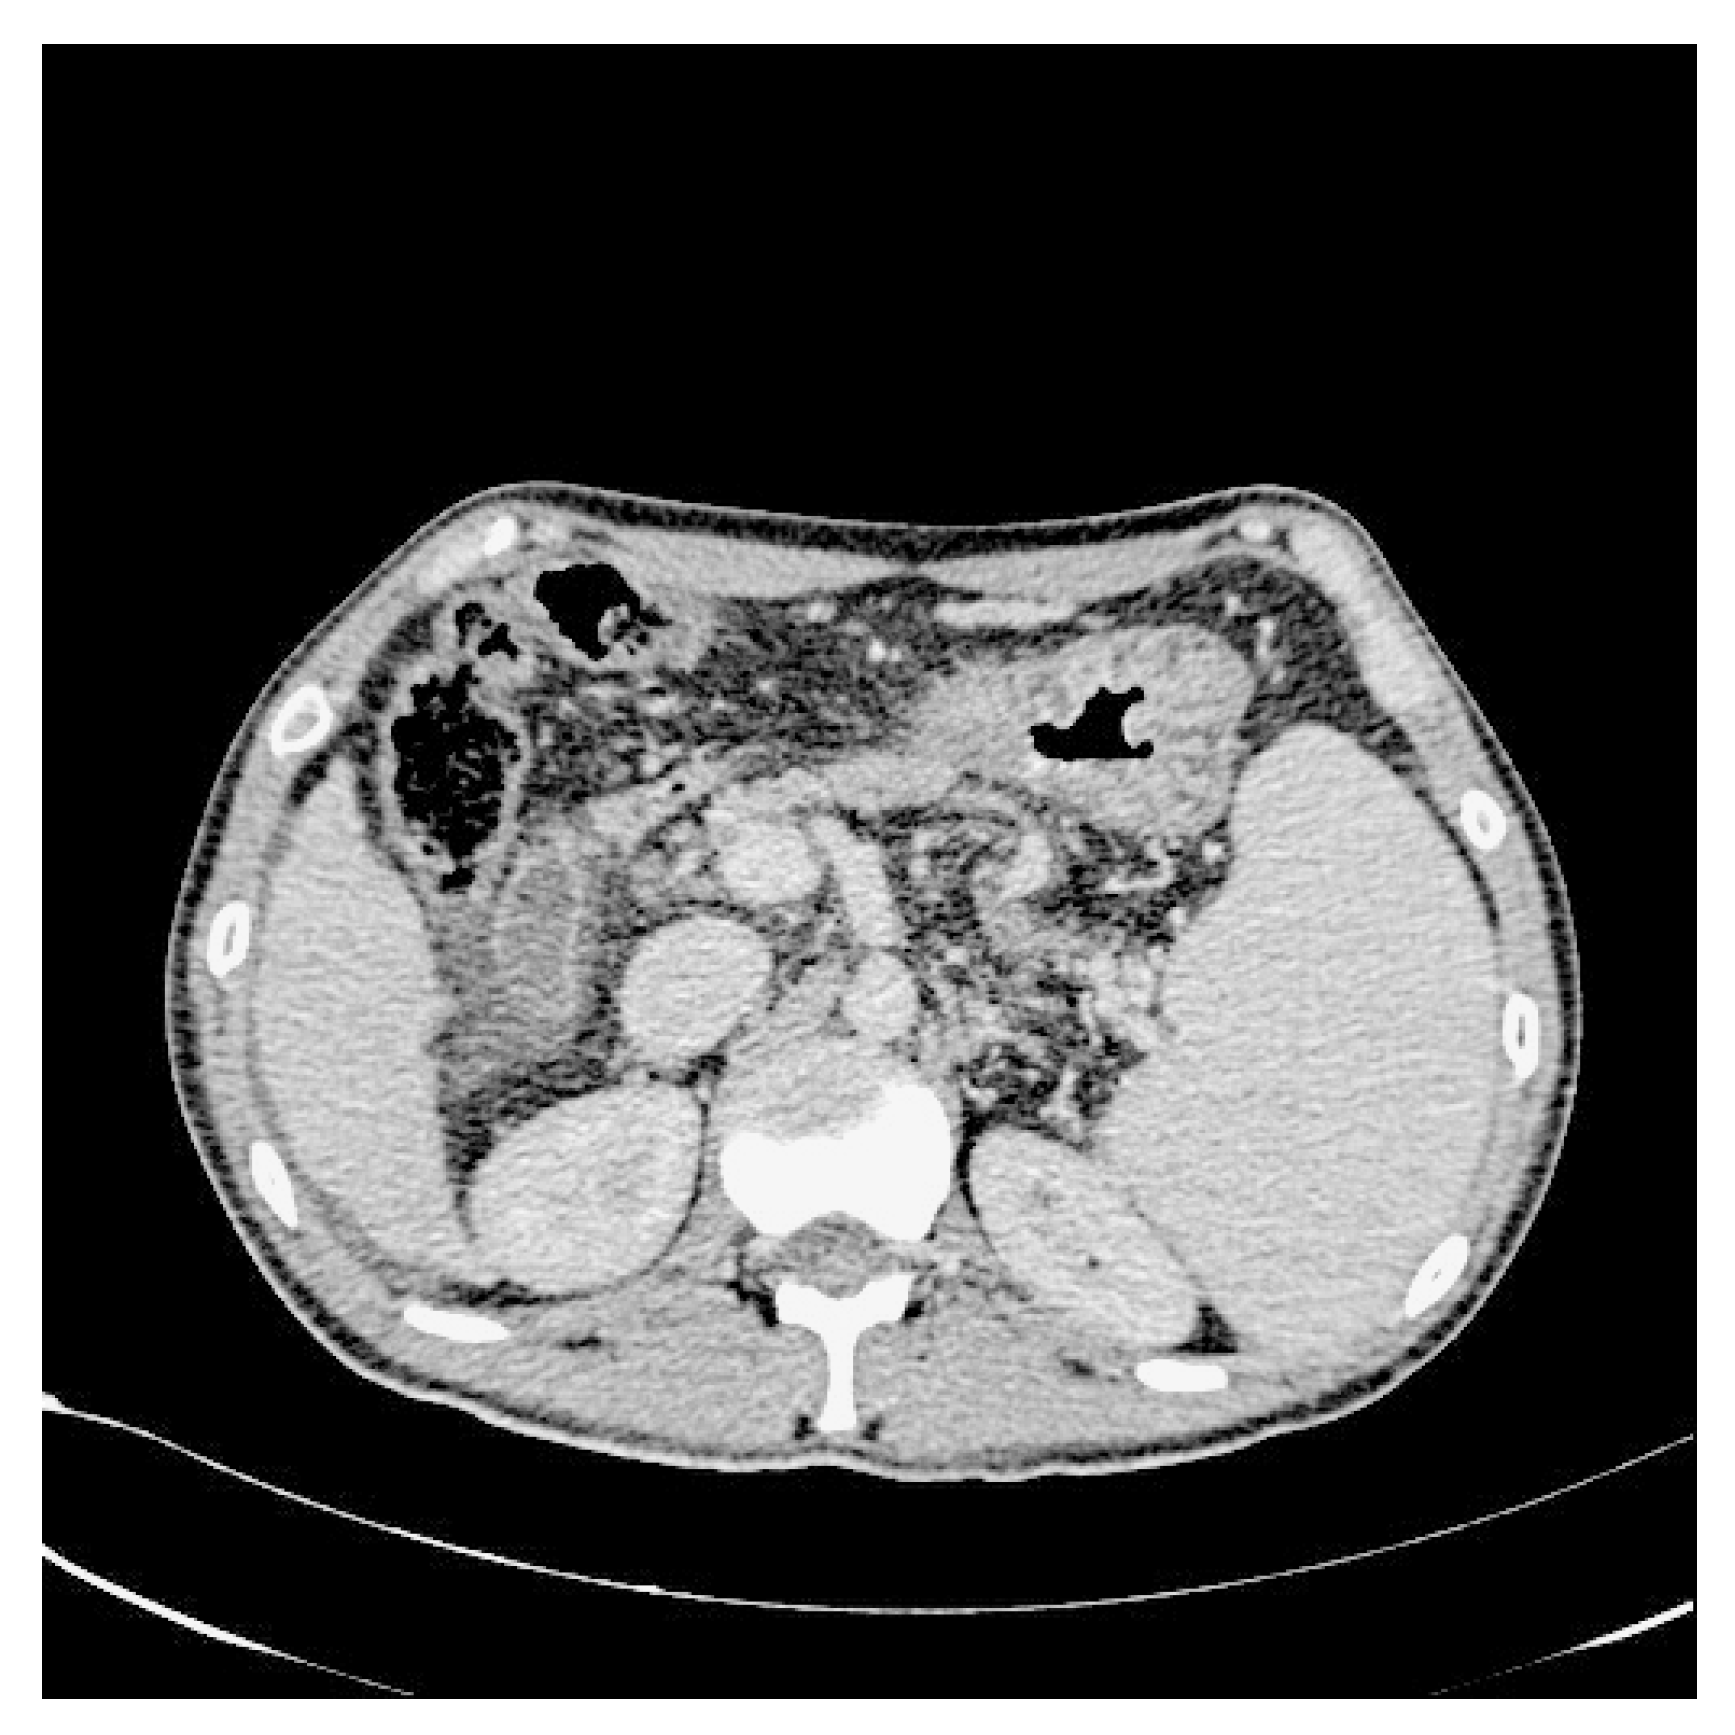

In addition, we used WGIF [38] to enhance the picture and obtain an image with stronger texture features to facilitate training after completion. Figure 3 and Figure 4 illustrate the comparison between the original and enhanced images, showcasing the augmentation of strong classification texture features. The original image, as depicted in Figure 3, demonstrates limited texture details and a relatively lower discriminative potential. However, upon applying advanced image enhancement techniques, as depicted in Figure 4, the texture features undergo substantial enrichment, resulting in heightened discriminative capabilities.

Figure 3.

Original CT image.